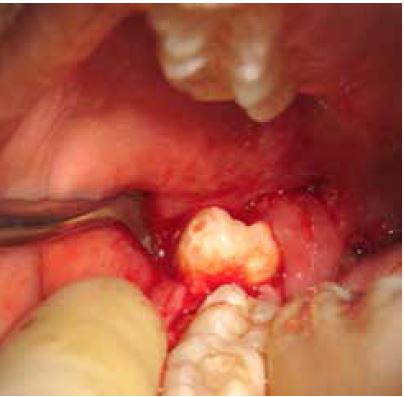

A continuación, se aplicó la regla de oro, que es observar completamente la corona, para ello se realizó osteotomía que es desgaste de hueso vestibular y distal que cubría parte de la corona, con fresa de carburo tungsteno redonda de tallo largo número (7). Una vez observada toda la corona colocamos el elevador recto en mesial para empezar a luxar las piezas; seguido por el elevador bandera en la furca haciendo movimientos de palanca, teniendo en cuenta que como son piezas fusionadas, la fuerza que se tiene que hacer, debe ser una fuerza controlada para facilitar la extracción (figura 4).